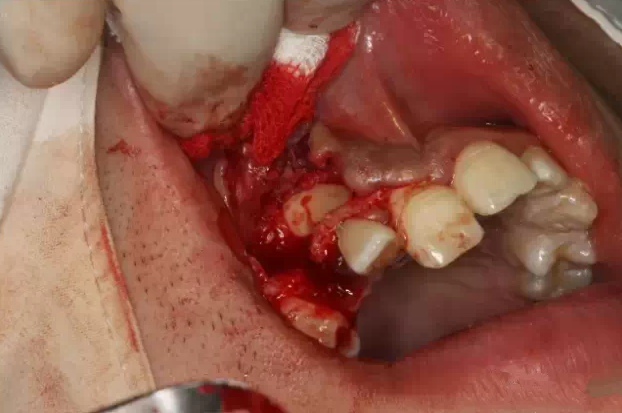

行唇側梯形瓣切開、翻瓣

QQ圖片20150730095024.png

骨鑿去除唇側部分皮質骨

QQ圖片20150730095038.png

弧形鑿沿正畸牽引路徑去骨,作用是去皮質骨化,保證13能順利牽引到正常位置。

QQ圖片20150730095051.png

暴露13唇面

QQ圖片20150730095139.png

清理牙冠唇側部分軟組織

QQ圖片20150730095158.png

止血、干燥

QQ圖片20150730095209.png